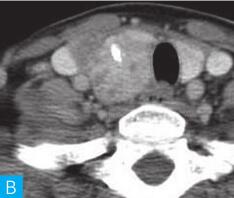

滤泡性腺瘤是甲状腺最常见的原发性良性肿瘤,其与结节性甲状腺肿伴腺瘤样增生均可表现为高、等或低强化,在影像学上极难鉴别,但前者多为单发结节、平扫密度均匀(图2),而后者则多为多发结节、密度不均,一旦结节性甲状腺肿伴腺瘤样增生表现为单发结节,两者无法单纯通过影像学进行鉴别。

图2 滤泡性腺瘤:A.颈部CT横断面;B.颈部CT横断面增强